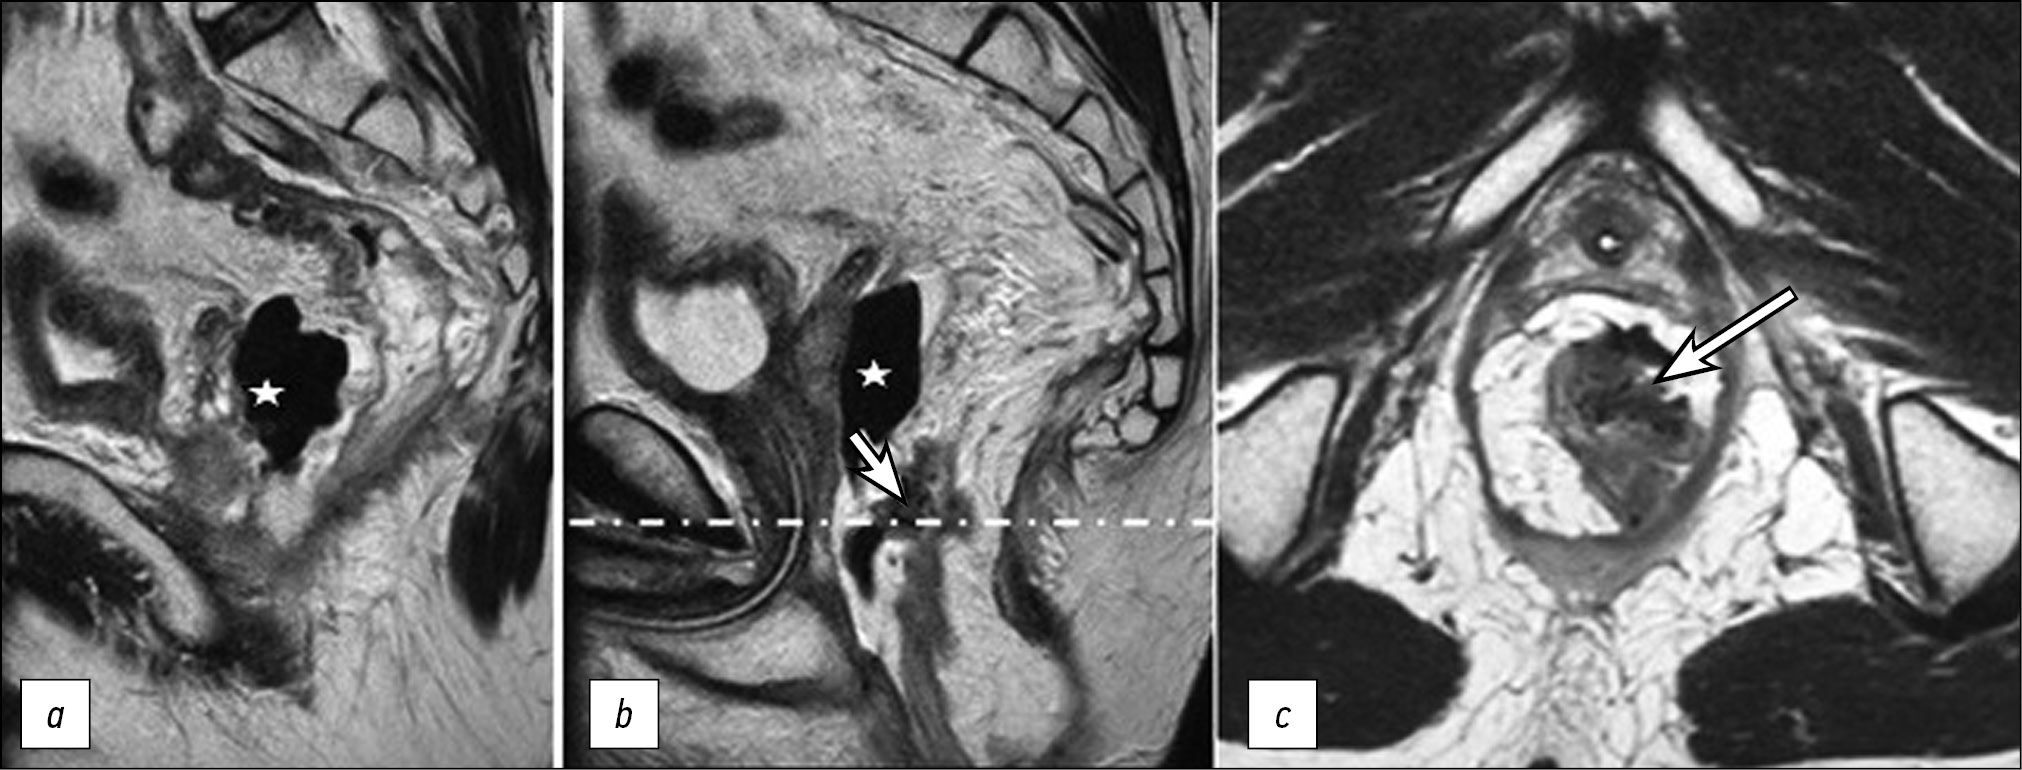

Fever up to 37.8℃ persisted on POD 10, but the CRP level decreased to 78.8 mg/L. A persistent defect in the wall of the coloplasty pouch with a parietal air-filled cavity was observed on a follow-up contrast-enhanced MRI; no contrast uptake was observed in the pulled-through colon segment (Fig. 5).

Figure 5. Pelvic MRI scans in Т2 mode (a) and 1-FS mode with contrast enhancement at the level of the dashed-dotted line in the axial plane (b) on POD 10: a defect in the wall of the coloplasty pouch (arrow) and an air-filled cavity (asterisk); two adjacent sagittal sections in 1-FS mode with contrast enhancement (c, d): the upper and lower edges of the ischemic colon segment (arrows).

Necrosis of the pulled-through colon segment, which necessitates emergency surgery, is an unfavorable outcome of acute ischemia. In our case, a follow-up MRI (POD 6) revealed diffuse edema in the pulled-through colon segment wall that persisted and an area of tissue destruction appeared. A defect containing fluid and gas formed in the wall of the coloplasty pouch. Changes in the MRI pattern were detected on POD 10 despite ongoing conservative therapy. A follow-up endoscopic examination confirmed the MRI findings of necrotic changes. Additionally, signs of a general inflammatory response increased, necessitating relaparotomy with disconnection of the anastomosis and resection of the necrotic portion of the colon.

Follow-up MRI revealed signs of total necrosis of the entire intestinal wall with destruction and the formation of a parietal cavity containing fluid and gas. MRI signs of total intestinal wall necrosis in combination with relevant clinical and laboratory findings should be considered an indication for relaparotomy.